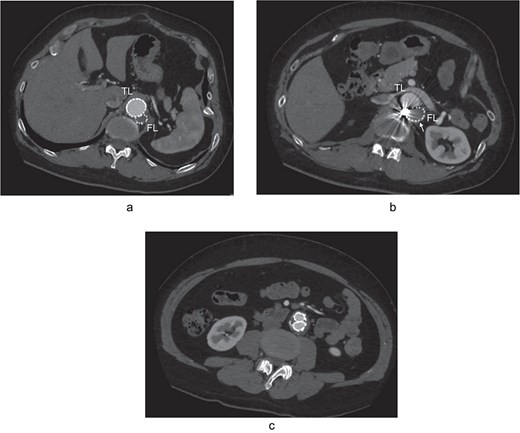

At 2-year post-procedure, CT follow-up showed AAA expansion to 56 mm, and FL dilation to 25 mm. The contrasted CT showed small inflow to the FL from the TL through the gap between the intimal flap and the FL stent graft via a residual intimal tear, as well as reversal flow from re-entry at the EIA (Fig. 2a–c). A second-stage endovascular repair was planned for completing the TAAA repair. Under local anesthesia, the gap between the FL stent graft and the intimal flap was occluded using DELTAFIL (Jonson & Jonson, NJ, USA) from FL side to close a residual intimal tear (Fig. 2d). The eighth intercostal artery and the third lumbar artery were occluded using DELTAFIL and GARAXY G3 (Jonson & Jonson, NJ, USA), respectively to block the backflow from these side branches. Then the 8 × 59 mm VBX (WL Gore & Associates, Newark, DE, USA) was deployed at left EIA covering the re-entry tear, successfully completing FL closure (Fig. 2e). The postoperative course was uneventful, with no paraplegia, and he was discharged on the postoperative day 4. The postoperative contrast-enhanced CT showed no contrast inflow into the FL. The CT imaging 3 years after the procedure showed the reduced diameter of abdominal aorta of 35 mm (Fig. 3a–c).

The contrasted CT 3D reconstruction 2 years after the false lumen (FL) stent graft placement (a; white arrow); the contrast-enhanced CT axial images showing small inflow to the FL from the true lumen through the gap between the intimal tear and the FL stent graft (b; arrow), and abdominal aortic aneurysm expansion to 56 mm (c; white arrow); the intraoperative angiography showing coiling of the gap between the intimal tear and FL stent graft (d; white arrow), and the VBX was deployed at left external iliac artery covering the re-entry tear (e; white arrow). TL: true lumen; FL: false lumen; SMA: superior mesenteric artery.